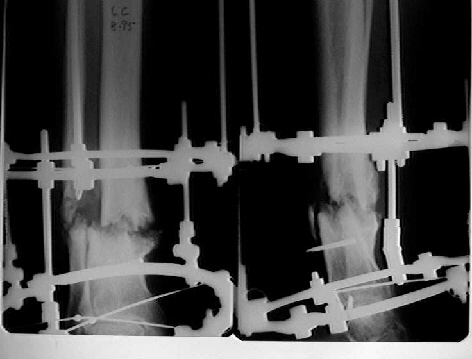

Female. 65 years old. 2 years ago trimalleolar fracture left ankle. First ORIF failed. Second ORIF with autologous graft at the fibular fracture was complicated by infection. The X-ray pictures show the actual situation. What are the suggestions of the group?

It seem a stiff pseudarthrosis. I will do a axial correction and lengthening if necessary with Ilizarov frame without any corticotomy. Probability of success will be 100% and relapse of infection 0%. You can see one case attached.